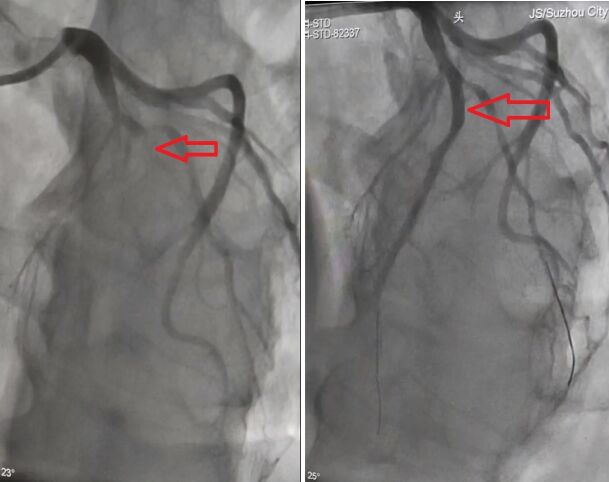

在履行完签字后,在张孝忠主任带领下,全科医护人员通力配合,手术顺利成功,在闭塞的左前降支植入三枚支架,开通了闭塞血管,手术用时仅四十八分钟。术后,患者胸痛好转,生命体征平稳,送回CCU继续恢复治疗,复查心电图提示前壁导联ST段抬高回落,正在康复中。